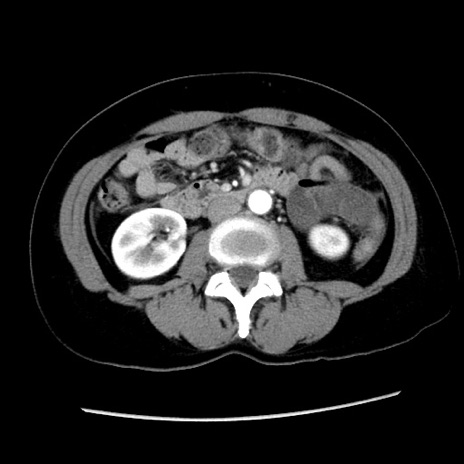

冠状断像

矢状断像